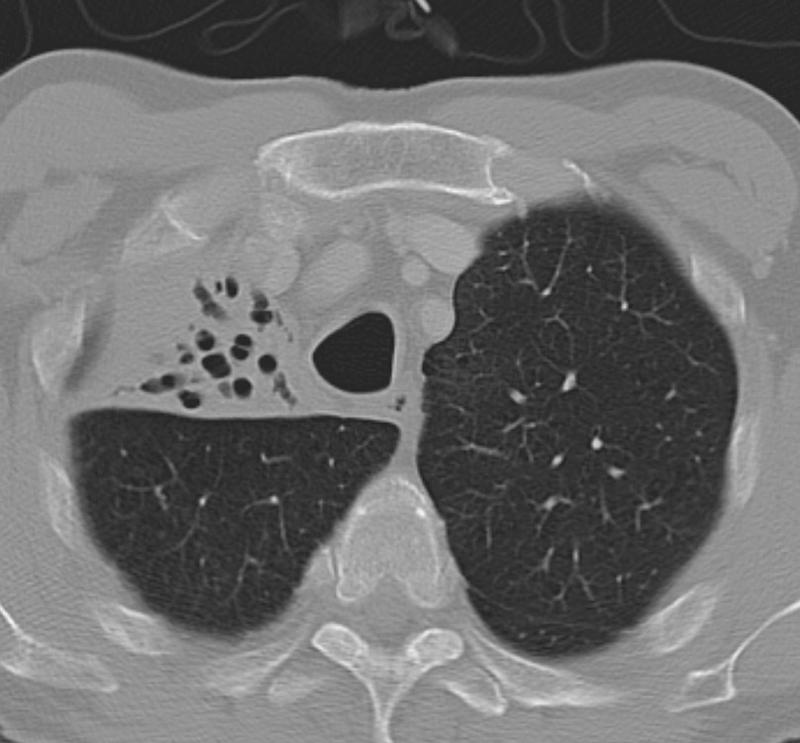

RUL Collapse Case 9 CT